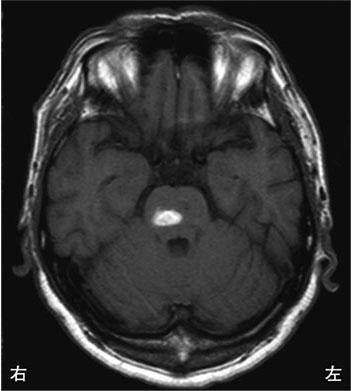

55歳の男性。突然のめまいを自覚し、歩行困難を呈したため搬送された。頭部MRIのTI強調像を示す。みられる所見はどれか。

1

JCSⅢ-100

2

左顔面の痛覚低下

3

左上肢の小脳失調

4

右上肢の運動麻痺

5

左下肢の深部感覚低下